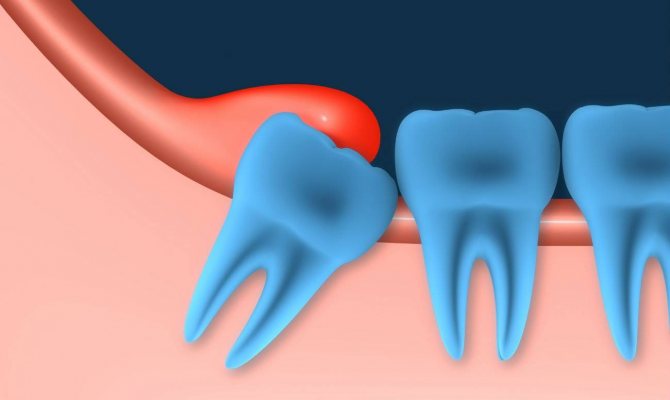

Одним из наиболее распространенных осложнений является воспаление дёсенной ткани над моляром и формирование так называемого капюшона, в котором может развиваться инфекция.

Под образование легко попадают мелкие пищевые фрагменты, извлечь которые оттуда самостоятельно зубной щеткой невозможно. В нем создается благоприятная для микроорганизмов среда, деятельность которых впоследствии приводит к инфекционному процессу на этом участке.

Основная опасность формирования над прорезывающимся моляром капюшона – возможность проникновения под него мельчайших частиц пищи, которые практически невозможно удалить посредством обычных гигиенических процедур.

Эти пищевые частицы становятся местом развития и размножения патогенной микрофлоры, при взаимодействии с которой начинаются процессы гниения, вызывающие развитие инфекции.

Когда растет зуб мудрости, происходит разрыв десневых тканей. В итоге отрывается кусочек десны, образовывая складку слизистой оболочки над третьим моляром. Именно ее стоматологи и называют капюшоном.

«Восьмерки» труднодоступны для чистки. Поэтому под капюшоном постепенно скапливаются частички еды. Со временем они начинают гнить и бродить. Это создает благоприятную среду для размножения условно-болезнетворных бактерий, входящих в состав микрофлоры ротовой полости: бактерий, грибков, микробов.

Из-за активности резко возросшего количества микроорганизмов начинает воспаляться капюшон. То есть, развивается перикоронит (перикоронарит). Основной симптом этой болезни – сильный отек оторванной части десны.